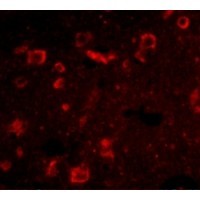

Supportive validation

- Submitted by

- OriGene (provider)

- Main image

- Experimental details

- Immunofluorescence of Slitrk6 in Human Brain cells with Slitrk6 antibody at 20 ug/mL.

- Validation comment

- IF